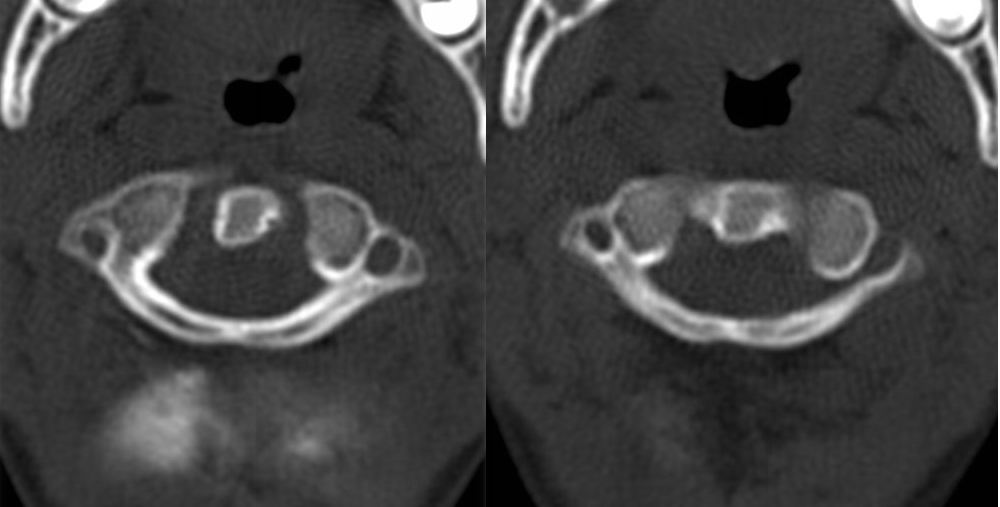

标题: PED1645:小孩寰椎问题

向各位请教:小孩子,6岁,寰椎两侧块前缘愈合了吗?不知道哪位老师能说说寰椎发育方面的问题.

环椎前弓裂

寰枢椎可以当做是独立于颈椎的一个部分,一般与枕骨相应结构称为枕寰枢复合体。寰椎有三个骨化中心,分别为前弓,后弓两侧,分别相当于颈胸腰椎椎体的椎体,双侧椎板。

发育过程为前弓出现齿突和双侧块骨化中心(特别说时,齿突在发育过程中是属于寰椎的,你可以把他当做“椎体“),后弓出现两侧骨化中心,齿突骨化后脱离前弓骨化中必与枢椎的齿突融合(这就是为什么会出现游离齿突的原因),齿突脱离时其其方还有剩余的软骨,此时两侧块前部也在向前骨化,当骨化完全时就形成齿突前结节,当不完全时就形成前弓裂(相当于我们平常诊断的如腰骶椎隐裂一样),同样,后弓也可以形成这样的裂隙。后弓与侧块联合处为椎动脉沟,此处有时可形成寰椎后弓桥(也有叫后弓孔、弓沟的)

寰椎骨化一般可以到10—12岁,所以现在在下结论说隐裂或发育异常为时尚早。